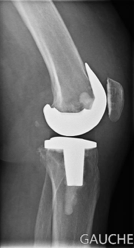

L'arthroplastie est dite totale quand on procède à un remplacement de toutes les surfaces articulaires au niveau de ces trois compartiments. On procèdera par conséquent à un remplacement de la surface articulaire fémorale, de la surface articulaire tibiale ainsi que rotulienne.

Entre la pièce tibiale et la pièce fémorale, on trouve le polyéthylène ( pièce en plastique) qui permettra le glissement de la pièce fémorale par rapport à la pièce tibiale.